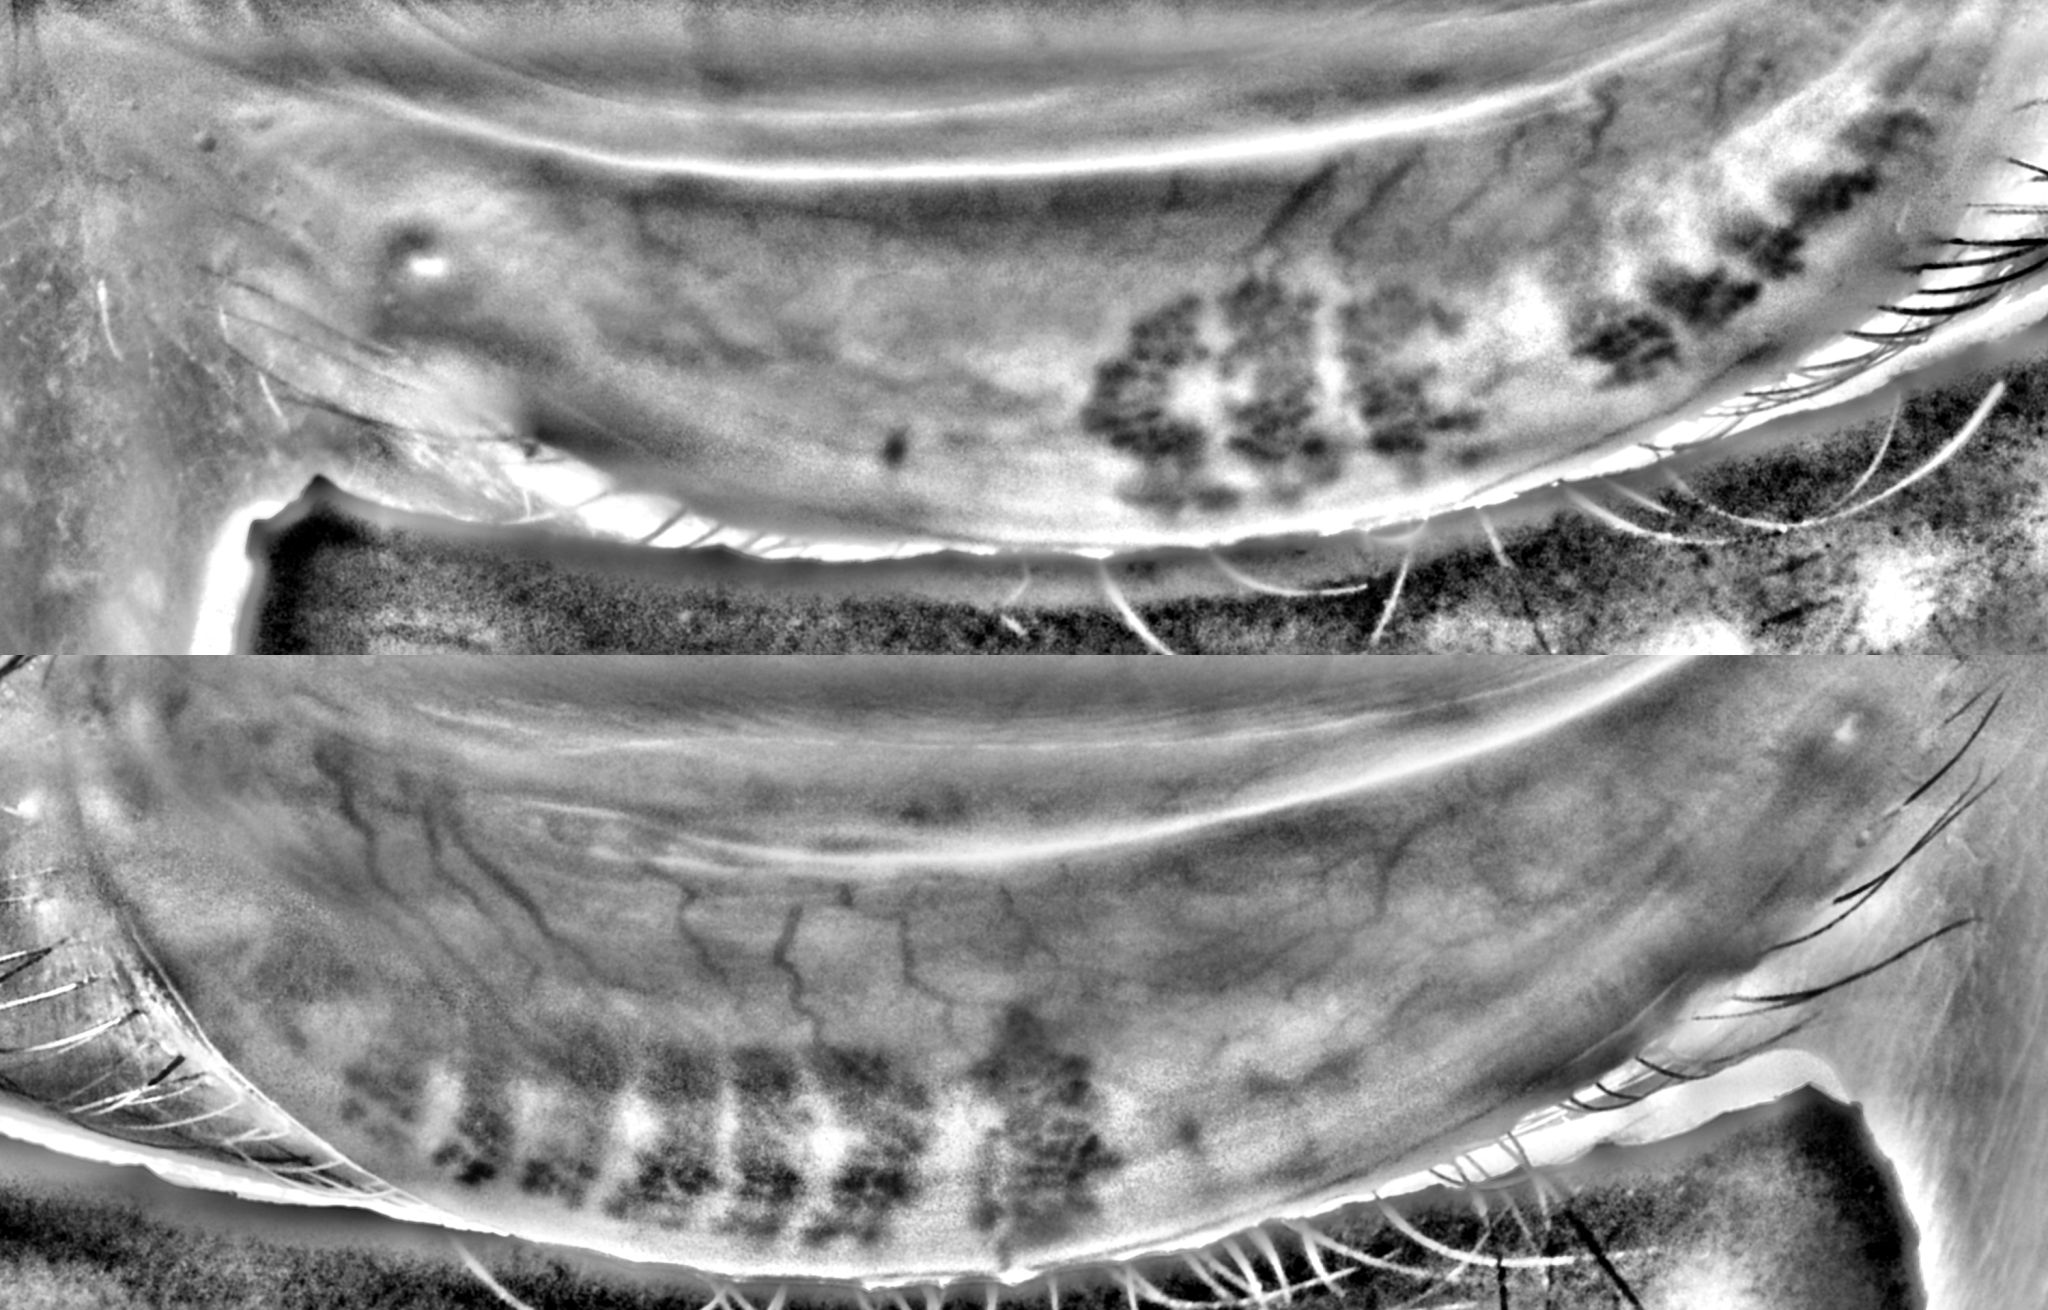

This meibography image was captured in a 31-year old female with no prior ocular disease and over ten hours of daily screen time , using a handheld MEA device.

Gland changes at this age raise an important question: Should meibography become part of routine eye examinations to detect changes earlier and slow progression?